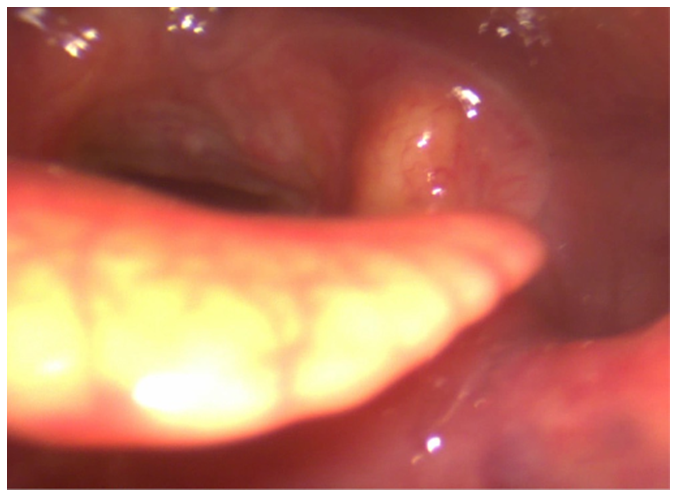

The ENT performed videoendoscopy with 0° rigid and flexible optic fibers. The findings from the videoendoscopy revealed significant abnormalities at the inner third of nasal fossae, pharynx, left tonsillar pillar, left part of soft palate, uvula, (Figure 1) epiglottis (Figure 2) but still sparing glottal and tracheal regions.

Figure 2 Mycosis involving tongue base, left glossoepiglottic vallecula , epiglottis, hypopharynx.